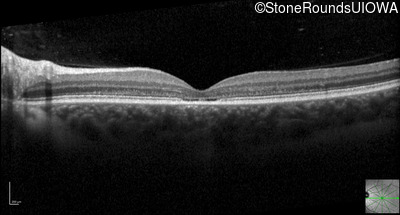

Optical Coherence Tomography - Right - 20/50 -2

Exemplar / OCT Stack

OCT Stack